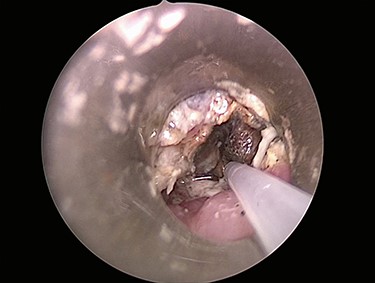

The patient was started on intravenous antibiotics and immediately taken to the operating room where micro-direct laryngoscopy, bronchoscopy and esophagoscopy were performed with removal of the 3-V, 20-mm button battery. The distal esophagus had near circumferential mucosal injury, sparring the posterior esophageal wall (Fig. 2). Bronchoscopy also showed superficial injury to the posterior wall of the right mainstem 3 mm in size without clear evidence of broncho-esophageal fistula.

Initial esophagoscopy showing the distal esophagus with near circumferential mucosal injury, sparring the posterior esophageal wall. The injury penetrated through the mucosa into the muscular layer.